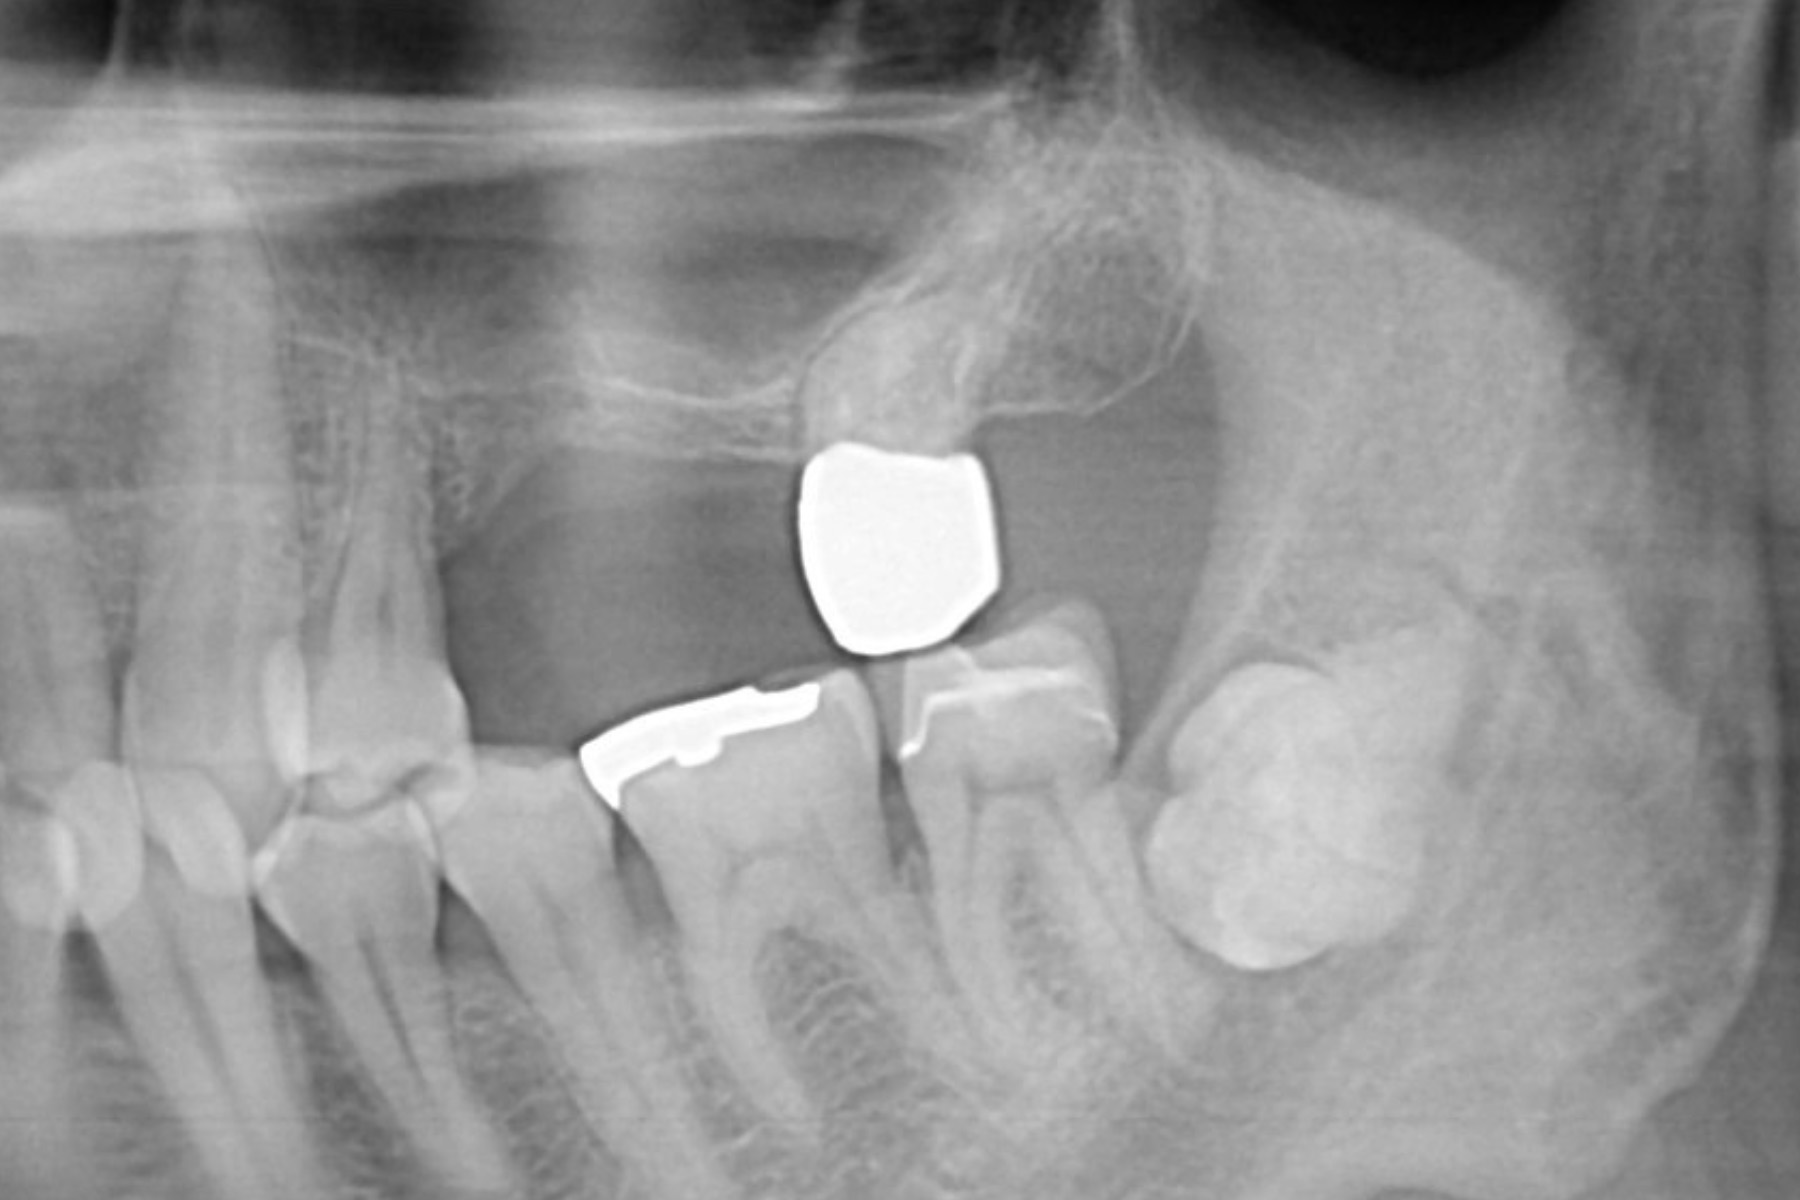

CASE16:抜歯即時インプラント

症例

CASE16